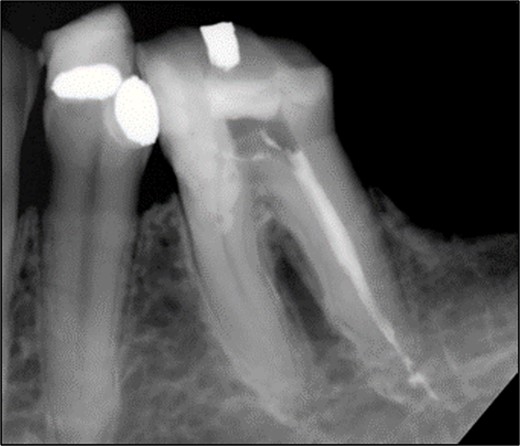

A 59-year-old male patient presented with a complaint of pain while biting on his lower left posterior teeth. Clinical examination revealed an extensive amalgam restoration on the lower left first molar (tooth 36) with a fractured restoration and secondary caries on the lingual aspect. The tooth was non-responsive to thermal testing and electrical pulp sensibility testing (EPT) and was tender to percussion. Radiographic examination showed radiolucency beneath the restoration on the mesial root surface, indicative of caries, along with furcation involvement and peri-radicular radiolucency. The tooth was diagnosed with pulpal necrosis and symptomatic apical periodontitis associated with extensive root caries (Fig. 6 and 7).

Periapical radiograph of tooth 36 shows large radiopacity, indicating a restoration on the crown extending to the mesial root surface. Radiolucency was detected beneath restoration on the mesial root surface, indicating caries. Peri-radicular radiolucency was observed in the furcation region.